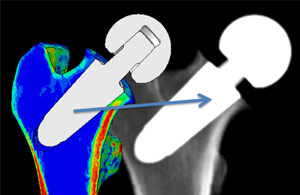

Virtual x-rays

"Virtual x-rays" generated for validation and use in conjunction with numerical bone remodelling analyses